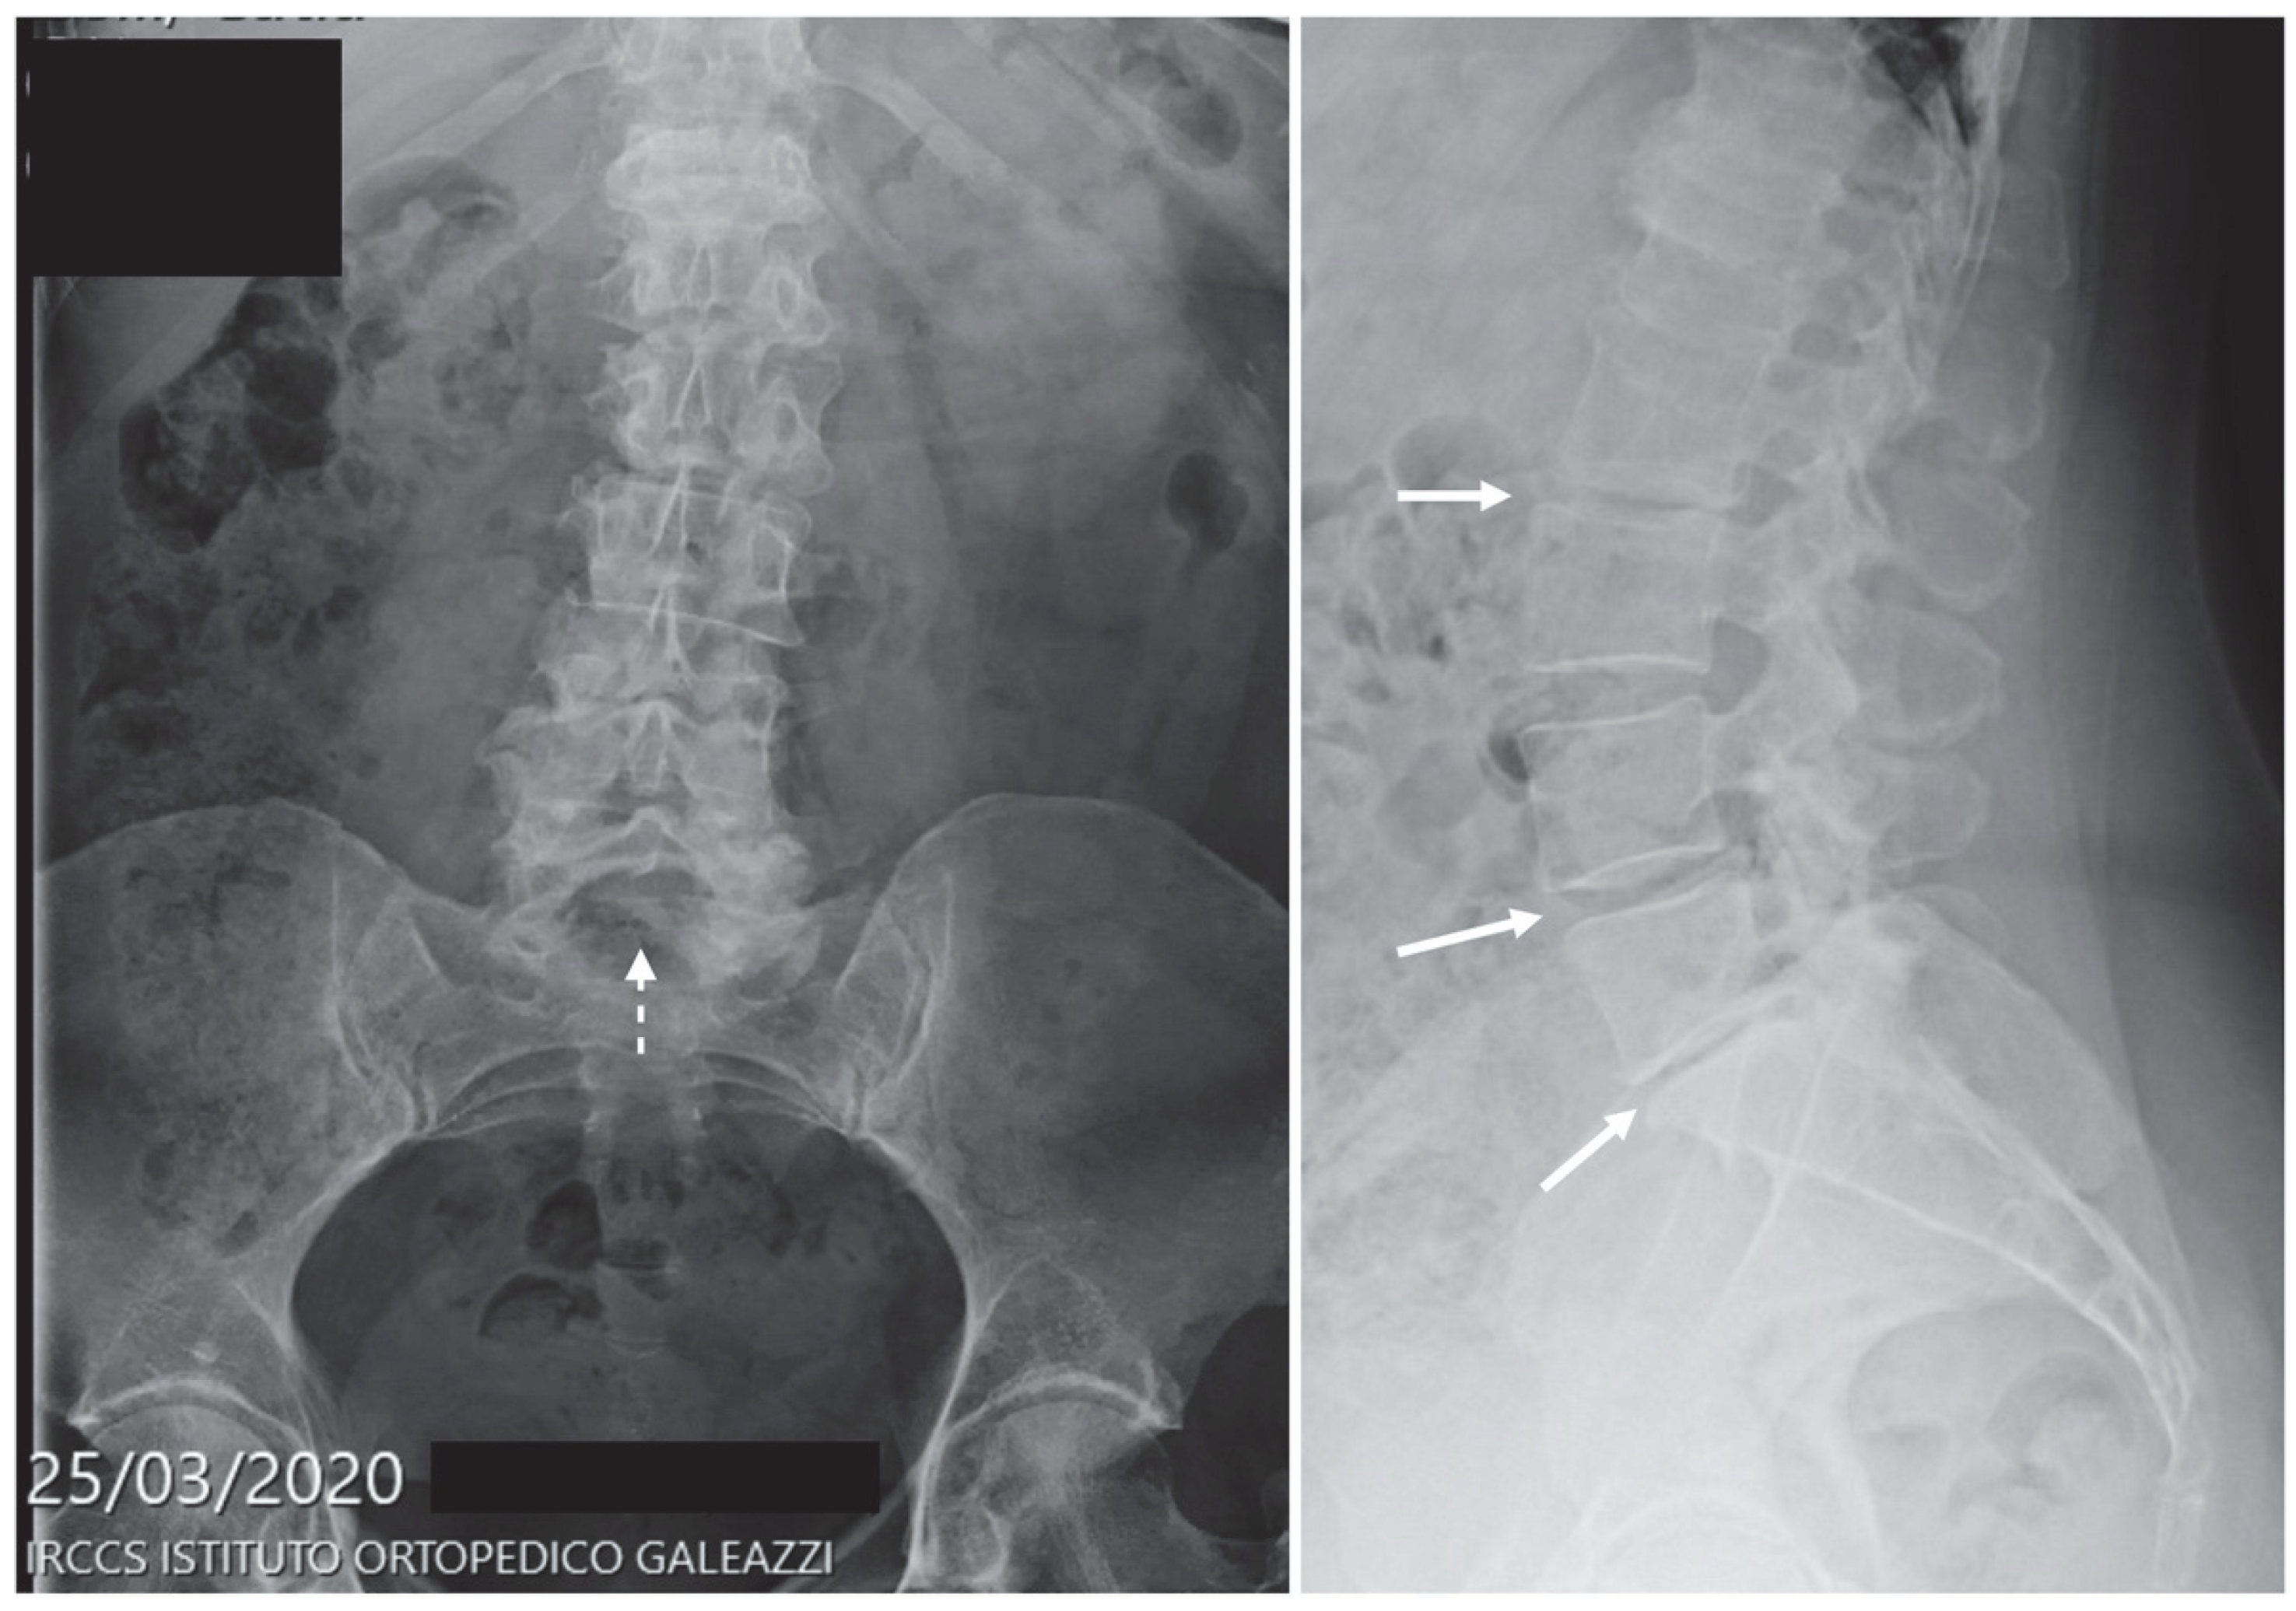

| Lower back pain | 70 | 2.8% | 171 | 3.7% | 303 | 4.8% | 384 | 4.9% |

| Sciatica | 36 | 1.4% | 96 | 2.1% | 142 | 2.3% | 242 | 3.1% |